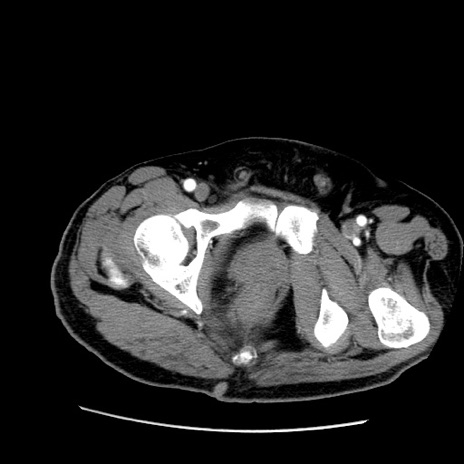

症例22(横断像)

【症例】50歳代男性

【主訴】腹痛

【現病歴】AVMからの被殻出血のため回復期リハ病棟入院中。 本日午後3時頃急に下腹部痛が出現した。

【既往歴】AVM、被殻出血、虫垂炎、高血圧

【身体所見】意識晴明、左半身不全麻痺、会話の理解は良好、36.5°C、腹部:膨隆、全体に板状硬、下腹部正中に圧痛点あり、反跳痛-、筋性防御不明、右下腹部にope scar

【データ】WBC 9400、CRP 0.06